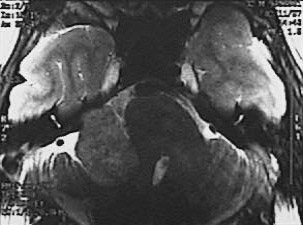

This magnetic resonance imaging (MRI) scan in transverse view demonstrates a mass impinging upon the cerebellum from the cerebellopontine angle. This is a schwannoma, also known as an acoustic neuroma because it arises from the eighth nerve.

Below is a magnified view of the acoustic neuroma.